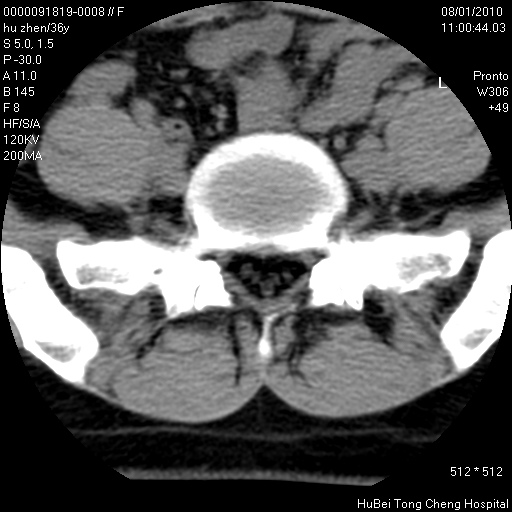

患者 女,36岁。右侧腰腿痛半月余。腰骶椎mr平扫偶然发现骶椎异常信号。

临床诊断:1)腰椎间盘突出症。2)骶椎肿瘤性病变?

骶椎ct平扫(层厚、层距均为5mm),图像如下:

考虑s1骨纤维异常增殖症。